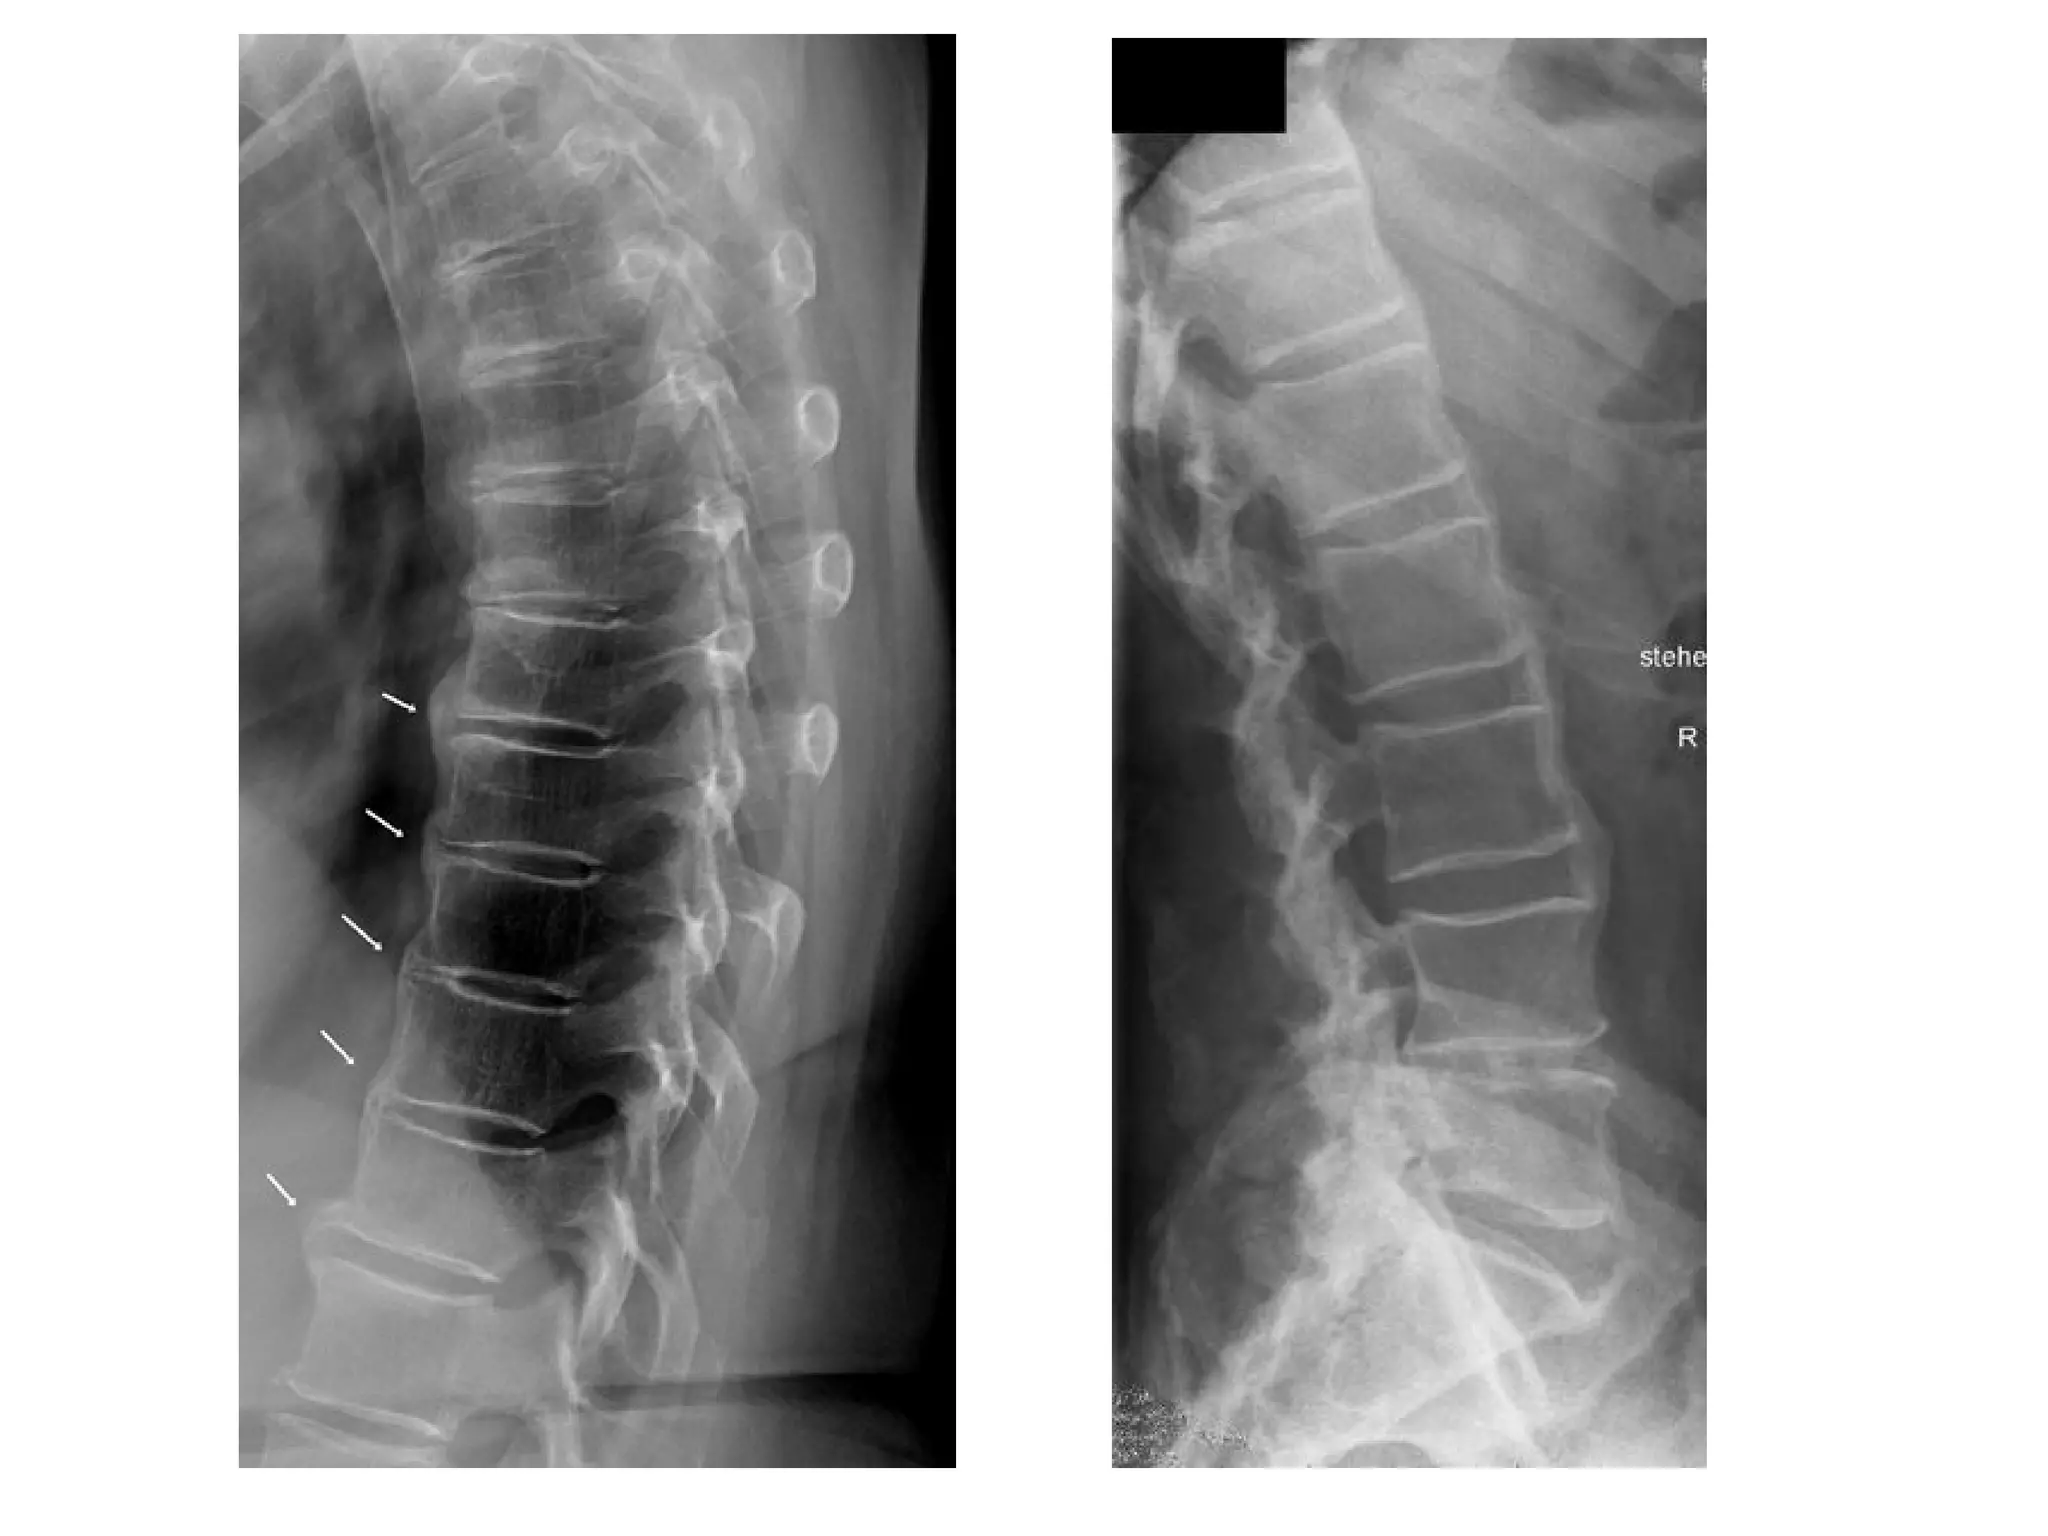

Spondylosis deformans , lateral radiograph of the lumbar spine reveals osteophyte

formation (arrows) , these initially extend in a horizontal direction and then in a

vertical one , severe apophyseal joint osteoarthritis is also present